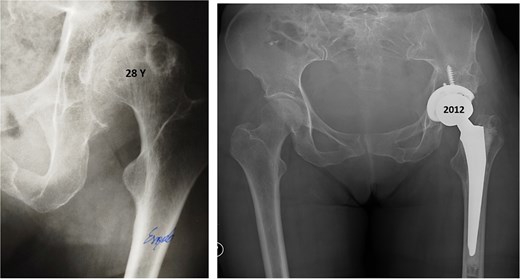

At 20-year follow-up, she presented with symptomatic hip pain. Pelvic radiographs (Fig. 2) showed signs of moderate osteoarthritis in the left hip (Tönnis Grade III). Radiographs showed signs of acetabular retroversion (ischial spine sign and posterior wall sign).

Postoperative radiographs of the pelvis 20 years after pelvic osteotomy, showing signs of moderate osteoarthritis in the left hip (Tönnis Grade III), and radiographic evidence of acetabular retroversion (ischial spine sign and posterior wall sign).